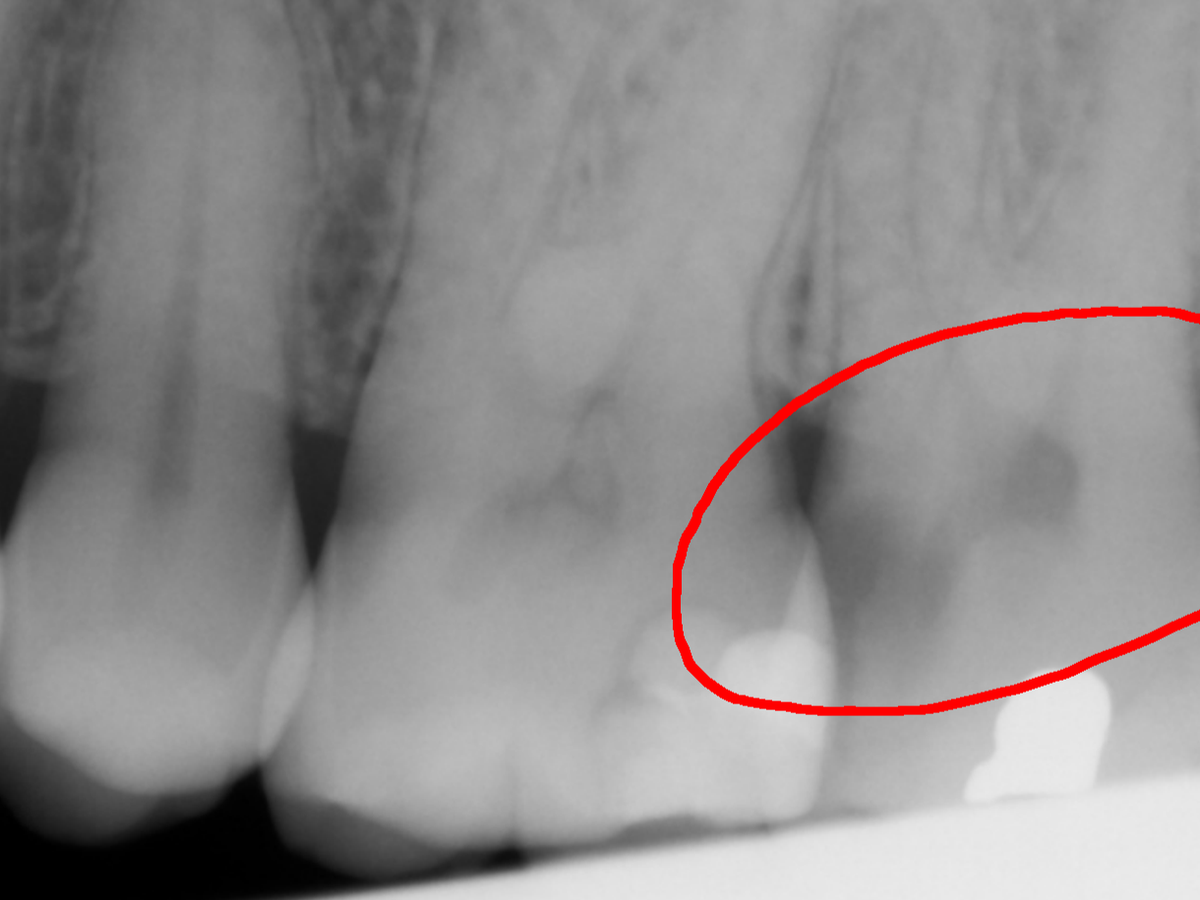

There is a further procedure she needs and the work was more extensive than what had been donated, so nearly all of the recipient's savings was used to pay for the procedures. She thought she would need one root canal, it turned out she needed four.

She fears there may be complications, but she is not sure.